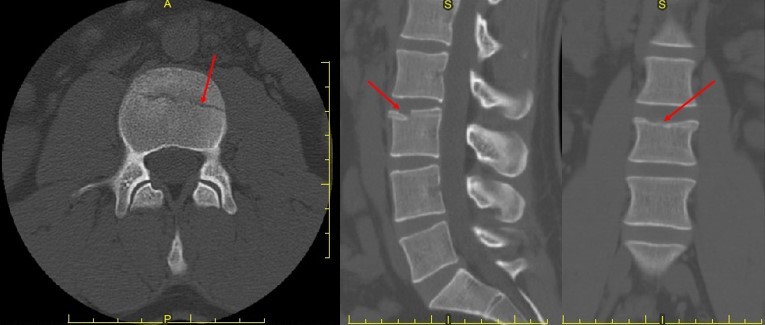

CT images of the lumbar spine revealed an acute comminuted fracture of the anterior, superior L3 vertebral body with no significant loss of body height, affecting less than 20 percent of the superior endplate. No retropulsion was noted.

CT images of the lumbar spine

Dr. Gregory immediately referred the patient to a medical orthopedist for follow up. The medical orthopedist prescribed pain medication, a brace and a light-duty work authorization not to exceed lifting objects greater than five pounds.